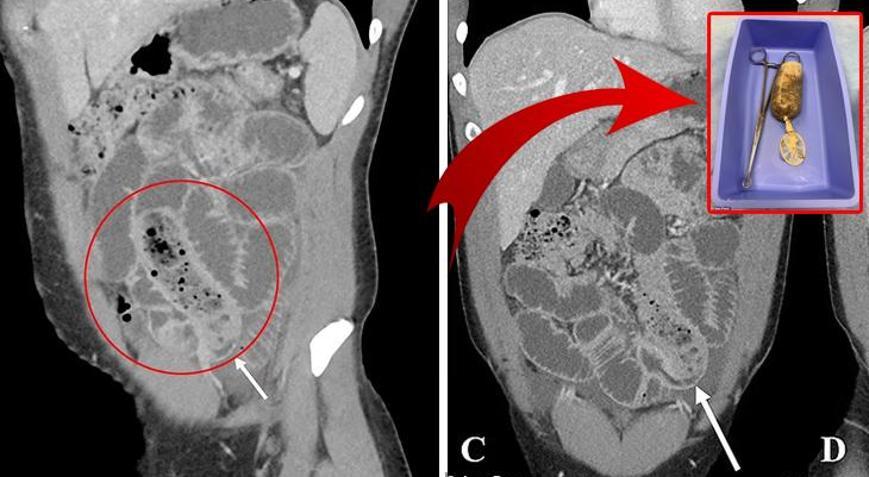

Daha sonra yapılan detaylı tetkikler sonucunda ilginç olay gün yüzüne çıktı. Söz konusu adamın ince bağırsağında kondoma sarılmış bir muz bulundu. Durumu gören doktorlar gözlerine inanamadı.

Röntgen çekilmesinin ardından hasta, apar topar ameliyata alındı. Doktorlar ameliyatın başarılı geçtiğini ve kondomla sarılmış muzun şahsın vücudundan çıkarıldığını aktardı. Doktorlar, hastanın bir öfke nöbeti geçirdiğini ve muzu bu sırada yuttuğunu düşündüklerini de belirtti.

ABD'nin önde gelen tıp dergilerinden olan Cureus da yaşanan olayı sayfalarına taşıdı. Söz konusu dergi, yaşanan olayı detaylı bir şekilde anlatarak adamın bağırsaklarının 24 saattir çalışmadığını ve ölmeye çok yakın olduğunu aktardı.